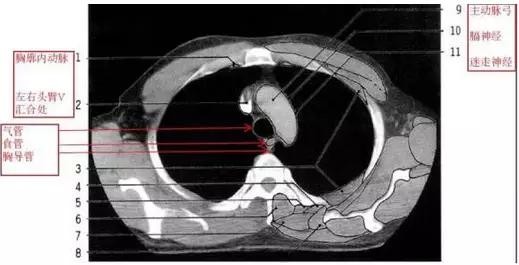

详尽的胸部CT影像示意图

胸部的CT是通过X线计算机体层摄影(CT)对胸部进行检查的一种方法。正常胸部CT层面较多,每一层面结构所表现的图像不同。下面是胸部CT图文示意图,可帮助临床医生详细了解CT结构。我们一起来看一下吧。